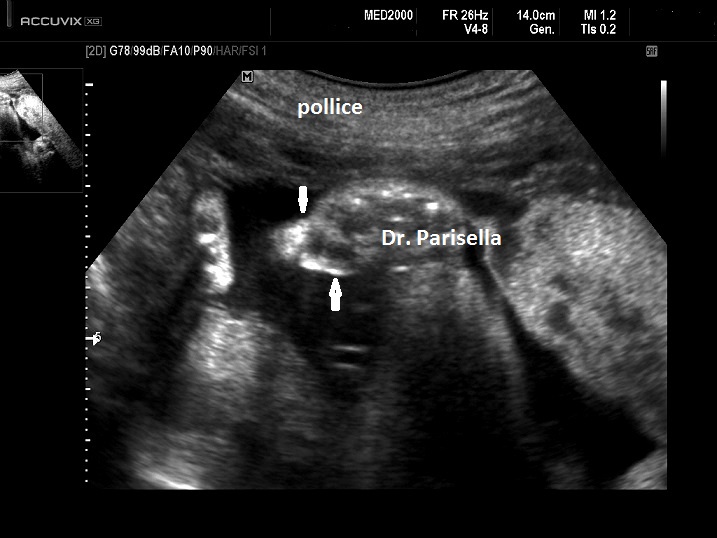

Team Rebecca - Home - Facebook Team Rebecca. July 23, 2017 · Figino Serenza, Italy ·. Rebecca è nata il 22 ottobre 2015 con la sindrome di Pfeiffer di tipo 2 (a quanto pare la peggiore). Inevitabilmente si passa tanto tempo in ospedale, ma cerchiamo ogni giorno di farle vivere una vita più normale possibile e ricca di possibilità. 390390. Sindrome di Pfeiffer: un caso clinico - Springer Healthcare ABSTRACT Oggetto: presentazione di un caso di sindrome di Pfeiffer di tipo 2 con valutazione delle caratteristiche cliniche, diagnostiche e dell'approccio terapeutico. Descrizione: riportiamo il caso di una neonata affetta da sindrome di Pfeiffer di tipo 2 con craniosinostosi, marcata proptosi bilaterale e ipertelorismo, sindattilia parziale e brachidattilia del secondo e del terzo dito ... Kenali Penyebab dan Tipe-Tipe Sindrom Pfeiffer di Sini ... Sindrom Pfeiffer merupakan kondisi langka yang hanya terjadi pada 1 diantara 100.000 bayi. Sindrom Pfeiffer terjadi ketika tulang-tulang tengkorak menyatu sebelum waktunya, yakni sejak bayi masih berada di dalam kandungan. Akibatnya, otak bayi tidak memiliki ruang yang cukup untuk tumbuh dan berkembang. Sindrome di Pfeiffer - #teamrebecca Sindrome di Pfeiffer. Dati epidemiologici L'incidenza annuale è 1/100.00. La malattia interessa maschi e femmine in uguale misura. Descrizione clinica La forma anomala del cranio viene di solito identificata nel periodo neonatale (in genere con l'ecografia prenatale). I segni cranici caratteristici comprendono l'ampiamento della volta ...

Sindrome di Pfeiffer - My-personaltrainer.it La sindrome di Pfeiffer è una rara malattia genetica caratterizzata da: La fusione prematura di una o più suture craniche. In medicina, questo fenomeno anomalo prende il nome di craniostenosi o craniosinostosi; La presenza di pollici e alluci anormalmente grandi e deviati in modo tale che sembrano allontanarsi dalle altre dita (deviazione mediale).